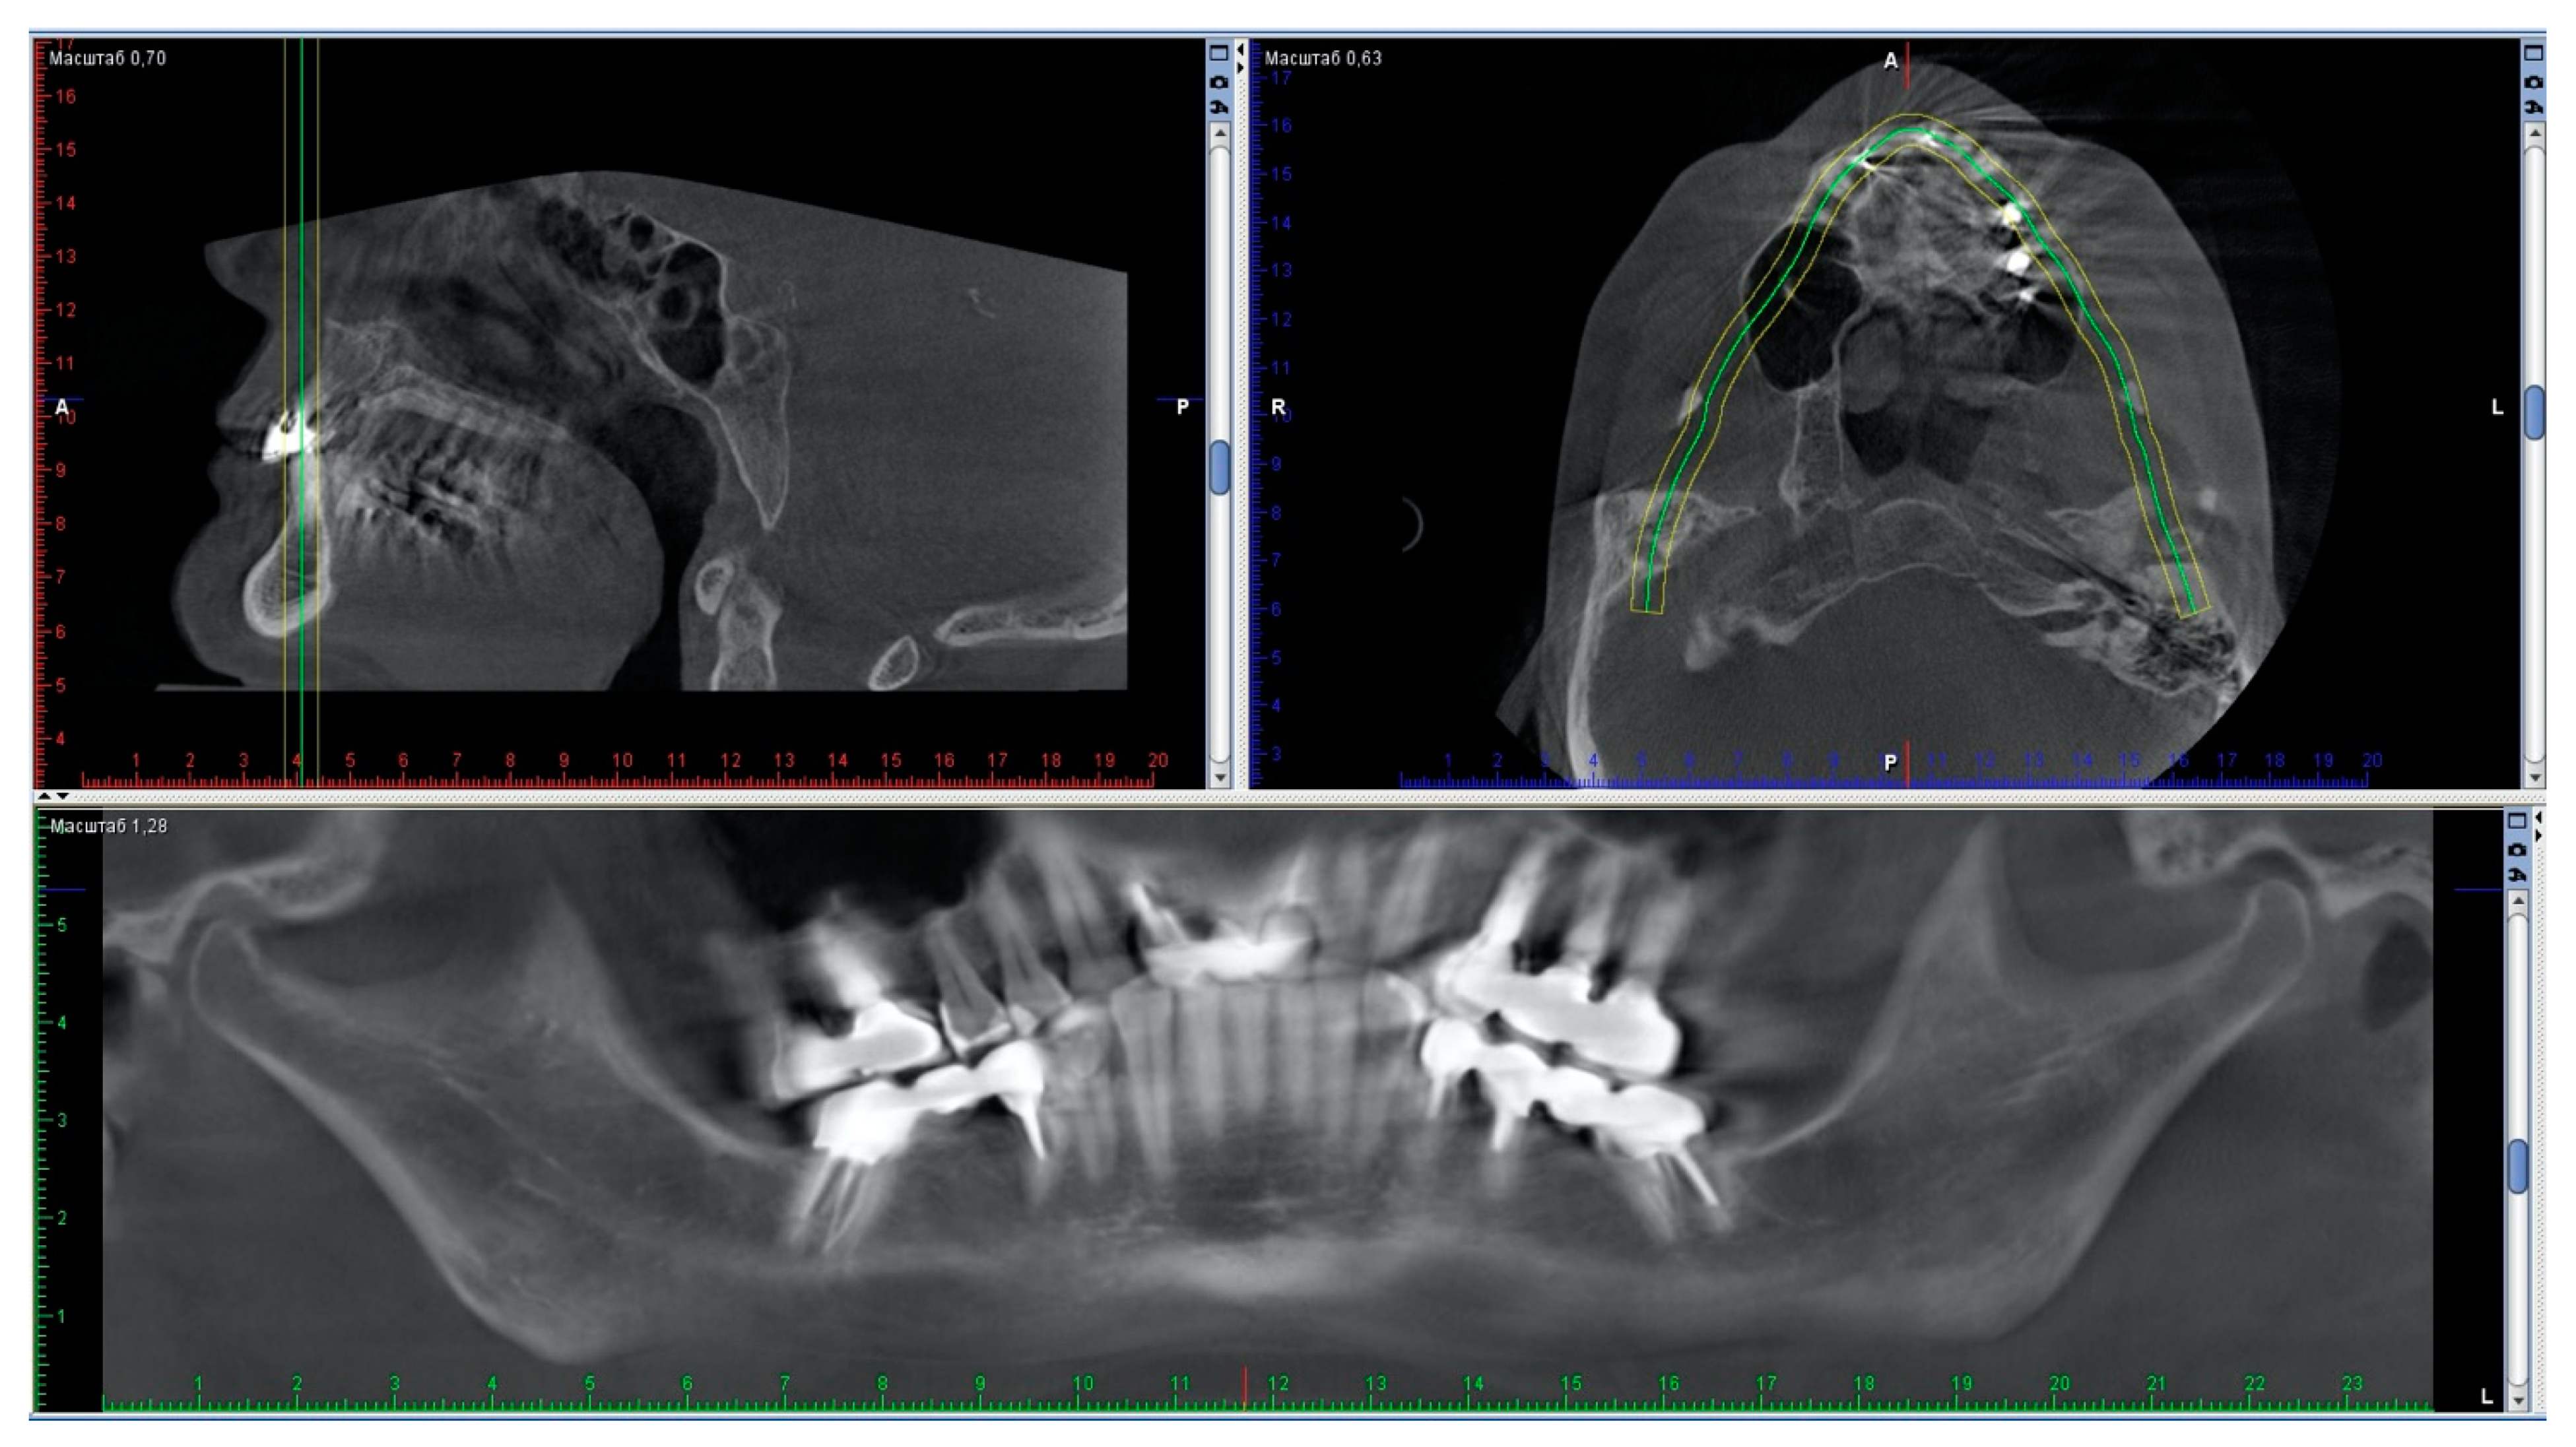

A second CBCT recorded while wearing the splint verified the match between virtually-planned and the actually-obtained mandibular positioning. The intra-articular space widths wearing the splint confirmed the achievement of the desired condylar position and the normalization of the values (Figure 8 and Figure 9). These results seem to validate the precision of this full digital workflow.

Figure 8. The position of the condyles adjusted by the repositioning splint (observed on the subsequent CBCT recording with splint). Note that it is very different compared with their position before treatment.

Figure 9. Normalization of the values of the intra-articular space widths assessed by the repeated CBCT, taken with a splint in the oral cavity.